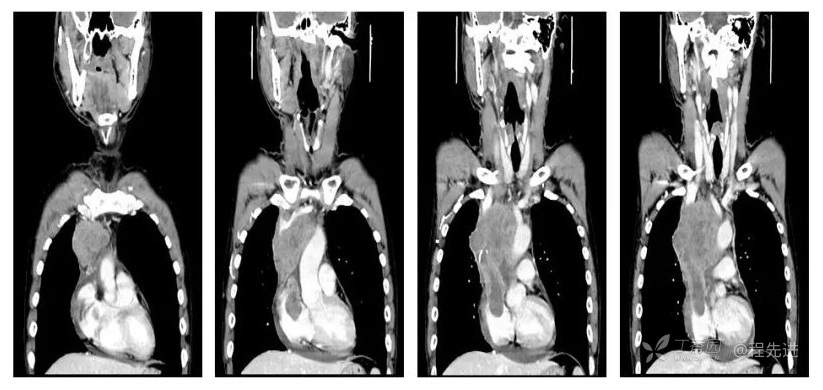

CT

平扫CT值约38HU,动脉期CT值约46HU,静脉期CT值约58HU